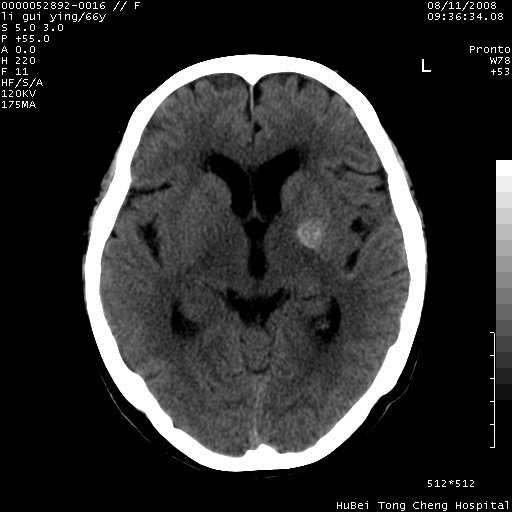

以下是引用sdzyy在2008-8-12 9:59:00的发言:[br]血管瘤可能性大

以下是引用代课学生在2008-8-12 9:48:00的发言:[br]考虑出血灶可能性大。

以下是引用yangyudong333在2008-8-12 12:22:00的发言:[br]1.病灶呈圆形[br]2.周围无水肿带[br]3.密度不均匀,内有点状钙化[br]4.无占位效应[br] 考虑良性占位性病变,血管瘤可能性大